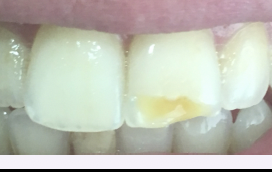

Tetracycline staining

● Tetracycline exposure during tooth mineralization binds to calcium ions, causing permanent tooth staining.

● Location and severity of the discoloration depend on the stage of tooth development at the time of

exposure.

● Staining typically appears as yellow, brown, or gray bands in affected teeth.

● Tetracycline is not recommended for children under age 8, as permanent tooth calcification is still

incomplete